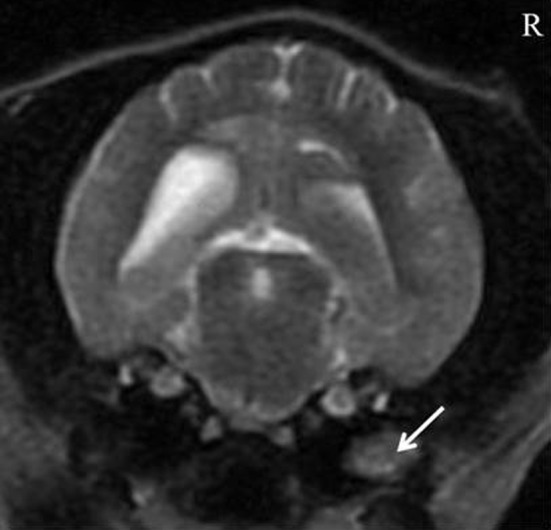

In a June 2022 article, German veterinary neurologists described the first reported case of a dog -- a 1-year-old cavalier -- diagnosed with anti-GABAAR (γ-aminobutyric acid-A receptor) autoimmune encephalitis. The cavalier (right) had multiple generalized seizures and showed alternating stupor and hyperexcitability, ataxia, repetitive muscle contractions, and circling to the left side. Auto-antibody encephalitis, with antibody-mediated dysfunction of receptors was suspected. Despite treatment with multiple antiseizure medications (diazepam followed by phenobarbital) the seizures and behavior abnormalities continued, and the dog alternated between stupors and hyperexcitability. Immunotherapy with dexamethasone, a corticosteroid, led to rapid improvement of the clinical signs and the CKCS improved continuously. A month later, GABAAR auto-antibodies had decreased significantly. An antibody search in the cerebral-spinal fluid (CSF) and serum located a neuropil staining pattern of GABAAR antibodies. At the examination four weeks after the start of immunotherapy, the dog was clinically normal; the GABAAR antibody titer in serum had strongly decreased; and the antibodies were no longer detectable in the CSF. The clinicians report that this is "the first veterinary patient with an anti-GABAAR encephalitis with a good outcome following ASM and corticosteroid treatment." They concluded:

"Based on the clinical signs and presentation (epileptic seizures lacking any response to ASMs, erratic behavioral changes) and the results of the initial diagnostics (lack of abnormal findings on conventional MRI and CSF examination), an autoimmune encephalitis was suspected, proven, and successfully treated. Clinicians should consider to test for autoantibodies and start immunotherapy in cases with a similar clinical presentation and lack of response to anti-seizure medication even if an inflammatory/infectious or neoplastic cause was clinically excluded on MRI and CSF."